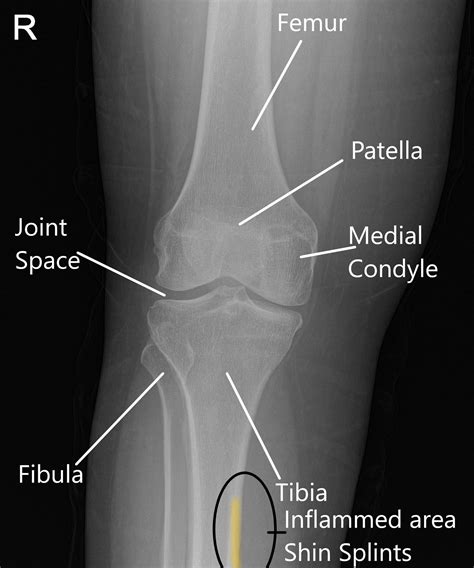

A Shin Splints Xray is a diagnostic tool that uses electromagnetic radiation to produce images of the bones and surrounding tissues. While X-rays are not typically the first line of diagnosis for shin splints, they can be useful in ruling out other potential causes of shin pain, such as stress fractures or bone tumors.

When a Shin Splints Xray is ordered, the radiologist will look for signs of bone abnormalities, fractures, or other conditions that might mimic the symptoms of shin splints. The X-ray can help differentiate between:

• Stress fractures: Small cracks in the bone that can cause similar pain

• Bone tumors: Abnormal growths that can cause pain and swelling

• Bone infections: Infections that can lead to pain and inflammation

• Shin Splints Xray: To rule out bone abnormalities